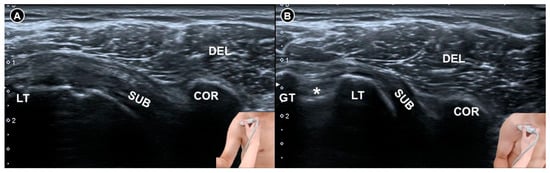

Tandon and colleagues [34] evaluated 90 individuals—comprising 30 patients with adhesive capsulitis, 30 with nonspecific shoulder pain, and 30 healthy controls—to compare dynamic sonographic findings with clinical evaluation and magnetic resonance imaging. Two experienced sonographers independently assessed the restriction of abduction and external rotation. Their results showed that restriction of external rotation (Figure 5) was a highly specific indicator of adhesive capsulitis, with a sensitivity of 86.2% and a specificity of 92.8%. In contrast, restriction of abduction was found to be nonspecific, with a specificity of only 6.7%. These findings suggest that dynamic assessment of external rotation is more reliable than that of abduction for diagnosing adhesive capsulitis.

Figure 5. Dynamic ultrasound imaging of the subcoracoid region during shoulder external rotation. In a normal shoulder (A), the subscapularis tendon is fully visualized whereas in a shoulder with adhesive capsulitis (B), only the distal portion of the tendon is visible and appears hypoechoic due to anisotropy, as the tendon fibers are not perpendicular to the ultrasound beam. The figure was redrawn by the authors with reference to Tandon et al. [34]. DEL, deltoid muscle; COR, coracoid process; SUB, subscapularis tendon; LT, lesser tubercle; GT, greater tubercle; asterisk, long head tendon of the biceps brachii.